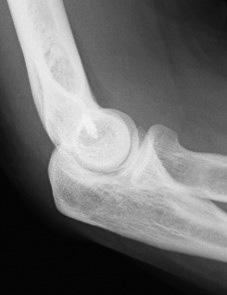

Figs. 11 y 12: Imágenes radiológicas de una paciente cocinera con rotura del ligamento lateral externo producida a los 2,5 años de la intervención. La reinserción se realizó con un arpón Mitek Super GII ® utilizando restos del propio ligamento y el tendón conjunto.

Parece muy probable que la frecuencia de complicaciones esté relacionada con la agresividad de la técnica empleada. Las tenotomías superficiales del tendón conjunto 18, así como las perforaciones del epicóndilo, las escarificaciones tendinosas (14, 19) o la denervación aislada (12,33) como únicos gestos tal vez resuelvan menos casos, pero también ofrecen menos complicaciones que la relajación tendinosa o la apertura articular concomitante. En este sentido, la técnica de Wilhelm (12,20) (propuesta en 1959 por Kaplan (34) y posteriormente modificada por Dellon (32)), puede ser más o menos suave según se realice una mera denervación del nervio cutáneo antebraquial posterior y ramas sensitivas del nervio radial, o se acompañe de una desinserción permanente de la musculatura extensora dejando sin reinsertar en su lugar de origen al tendón conjunto de ECRB y EDC. En nuestra experiencia, esta segunda variante de la técnica resulta más eficaz pero también más agresiva y con mayor número de complicaciones. En cualquier caso, aún en la simple denervación, tal como la describe Wilhelm se produce siempre una relajación muscular, especialmente del Extensor Carpi Radialis Longus (ECRL), porque la reinserción proximal de este músculo no es factible una vez desprendido completamente ya que no tiene tendón humeral; sus fibras se insertan directamente en el hueso mediante las fibras de Sharpey (Fig. 8) y, por otra parte, al realizar su desinserción con bisturí eléctrico –como propugna Wilhelm y así la hacemos también nosotros– se cauterizan las fibras impidiendo su reinserción y, por consiguiente, quedando distendido. Esta variante de la técnica de Wilhelm debe ser muy cuidadosa y requiere un gran equilibrio entre desinsertar lo suficiente la musculatura extensora como para relajarla, pero no tanto que se favorezca el desprendimiento de la misma y, desde luego, evitando siempre la lesión del ligamento lateral externo para evitar una inestabilidad iatrogénica. La desinserción del tendón conjunto debe realizarse con bisturí frío para apreciar la coloración de las fibras tendinosas y ligamentosas (Figs. 9 y 10). La lesión aguda del ligamento lateral en el curso del acto quirúrgico, aun siendo más susceptible de producirse con el empleo de técnicas quirúrgicas drásticas, como la relajación excesiva con esta variante técnica de Wilhelm (12,20), es fácil de reparar si se diagnostica en el momento, mediante su anclaje con puntos transóseos o con arpones. Hemos tenido esta complicación en dos pacientes; en una se reparó en el mismo acto quirúrgico mediante la reinserción con un arpón óseo; en la otra se produjo la rotura de forma tardía, pudiendo repararse del mismo modo (Figs. 11 y 12). En ambos casos las dos pacientes pudieron incorporarse a sus respectivos puestos. En cambio, la reparación de las lesiones del ligamento lateral externo con desinserción de la musculatura epicondílea produce una severa inestabilidad lateral del codo, cuyo tratamiento es arduo y provoca, con no poca frecuencia, una pérdida de extensión y la imposibilidad de reincorporación del paciente a su trabajo o actividad deportiva habitual, especialmente cuando la rotura se produce de forma tardía, al cabo de días o varias semanas tras la cirugía.

La inestabilidad externa como complicación postquirúrgica está ampliamente referenciada (35-37). La reinserción epicondílea de la musculatura desprendida a menudo no es posible si está muy retraída, y exige el refuerzo con plastias tendinosas. Llop-Corbacho (35) empleó en un caso un aloinjerto de tibial anterior de banco con aceptable resultado. Degreef y De Smet (36) trataron una luxación posterolateral del codo tras una intervención de epicondilitis con descompresión del NIP, mediante la reinserción del complejo ligamentoso externo al periostio reforzándolo con el tríceps y aplicando un fijador externo. Hemos tenido esta complicación en dos pacientes. En una de ellas, pescadera de profesión, la desinserción muscular se produjo al cabo de 6 meses de la intervención quirúrgica, tras su reincorporación laboral (Figs. 13-16).